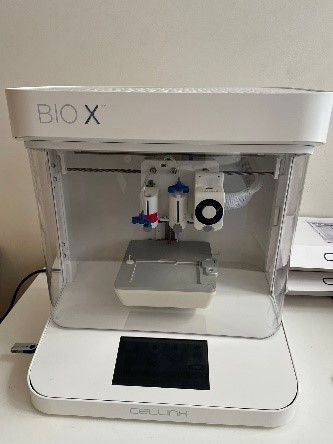

Fields of Study: Investigation of metabolic changes occurring in human metabolism and various organs by creating genome-sized models with 'Systems Medicine' approaches and identification of drug targets. Culturing yeast and mammalian cells using Lab-on-a-Chip technology. Investigation of cell-cell communication in cancer patients with organoid model and 3D bioprinting technology.

Field of Study: The focus of the work is on tissue regeneration, injectable scaffolds, drug delivery devices, 3D printing of tissue scaffolds and machine learning models for analysing biomaterial data.